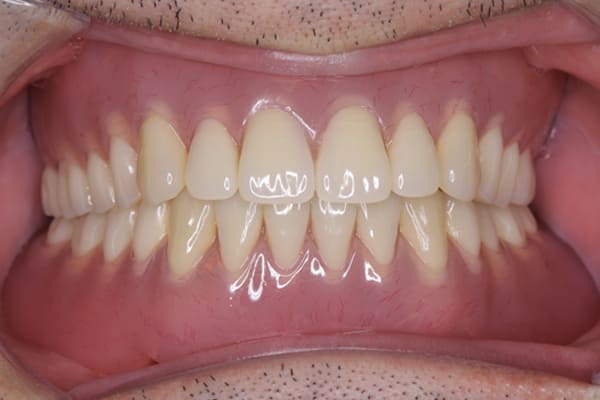

上顎に金属は用いていますが、外観に触れないため、機能性と審美性を持ち合わせた自然な口元になりました。

初めての入れ歯が総入れ歯の場合は、大きな違和感を感じられる方が多いですが、上顎に金属を用いた入れ歯にすることで、厚みを薄くし違和感を抑え、お食事での温熱も感じられるようになりました。

磁石を用いた入れ歯の設計により上下の入れ歯は、お食事やお歌を歌われ大きなお口を開けても外れない状態が可能になりました。

当初、ハンバーガーを召し上がりたいと仰っていましたが、今ではステーキも召し上がられ、カラオケでも入れ歯は外れず、滑舌が全く変わったと喜んで下さりました。